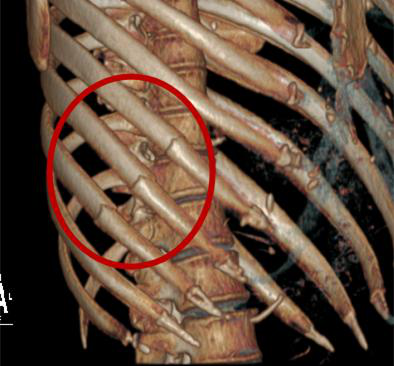

一、肋骨骨折的愈合过程

1

肋骨骨折10天内,骨折断端局部血肿形成,骨折线模糊,没有明确骨痂,这一时期称作“模糊期”;

2

骨折后11-20天,骨痂形成不明显,骨折线显示不清晰,隐匿性骨折检出率相对较低;

3

骨折后21-40天,骨折线断端内膜增生成骨,可见骨痂形成,大大提高了隐匿性骨折检出率;

4

骨折41天后,骨折断端内外骨痂增生,新生骨明显增多,骨痂密度增高;

5

骨折50天以后,骨膜反应逐渐消退,骨痂逐渐吸收、缩小。